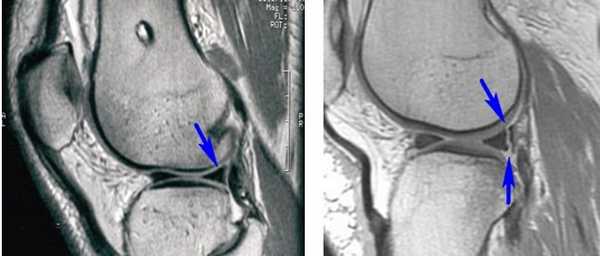

• Разрыв типа «ручки лейки» с дислокацией:

- На МР-томограммах при разрыве мениска типа «ручки лейки» в сагиттальной проекции отмечается дефицит заднего рога мениска (рис. 5, А) и симптом «удвоения задней крестообразной связки» за счет смещения поврежденной части мениска в межмыщелковую вырезку (рис. 5, Б). На другом сагиттальном срезе также виден смещенный в межмыщелковую вырезку фрагмент мениска (рис. 5, В)

• Лоскутный разрыв с дислокацией